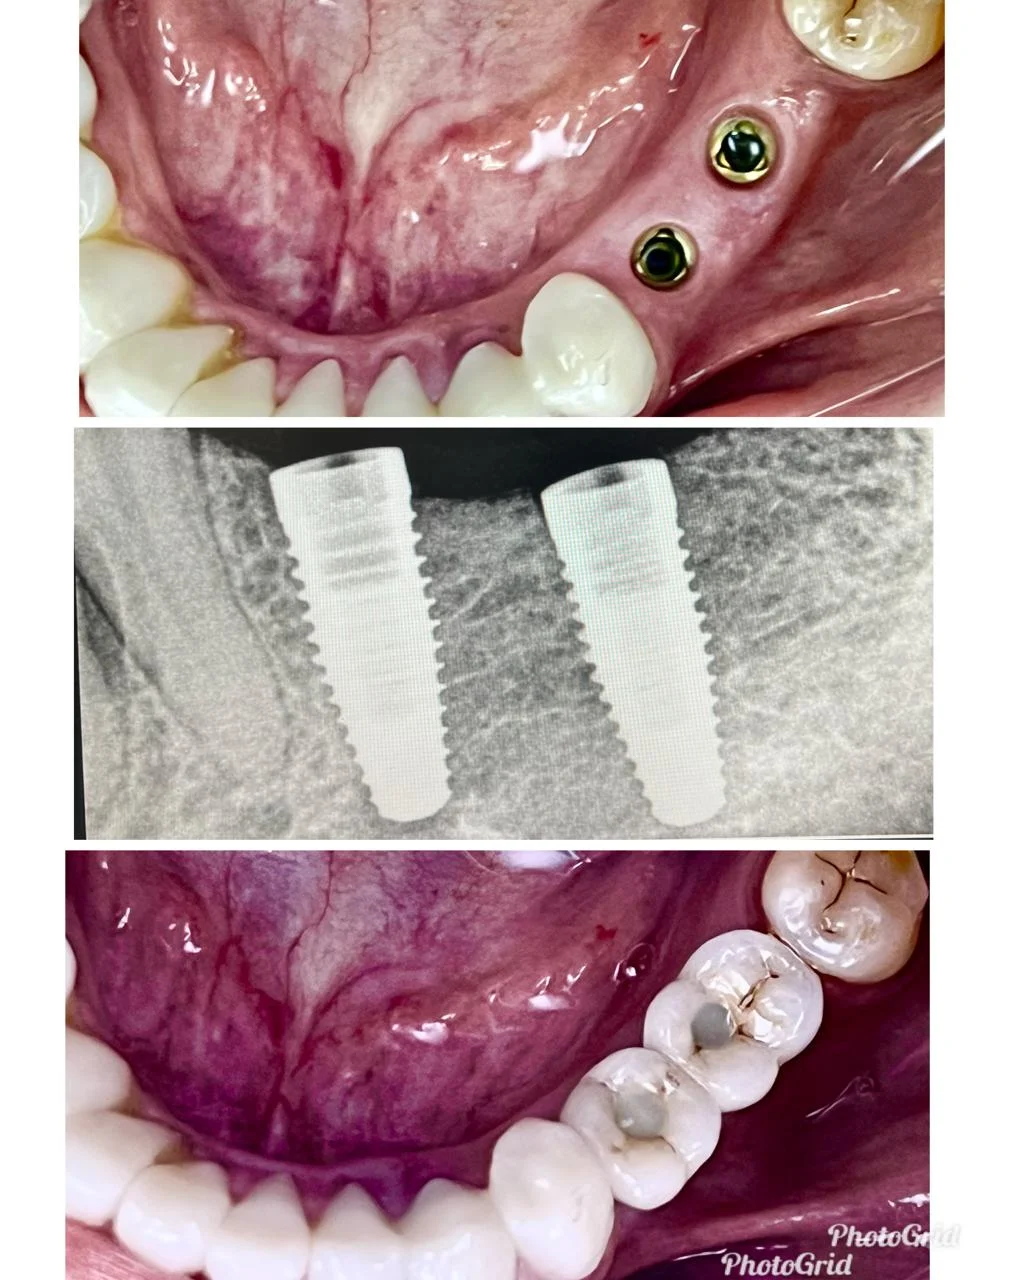

Showing Our Expertise In Dental Implantology

Single Tooth Implant

Single Tooth Implant with Crown